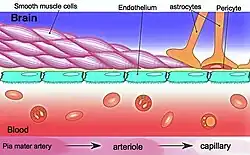

The blood–brain barrier (BBB) is a highly selective semipermeable border of endothelial cells that regulates the transfer of solutes and chemicals between the circulatory system and the central nervous system, thus protecting the brain from harmful or unwanted substances in the blood.[1] The blood–brain barrier is formed by endothelial cells of the capillary wall, astrocyte end-feet ensheathing the capillary, and pericytes embedded in the capillary basement membrane.[2] This system allows the passage of some small molecules by passive diffusion, as well as the selective and active transport of various nutrients, ions, organic anions, and macromolecules such as glucose and amino acids that are crucial to neural function.[3]

The BBB results from the selectivity of the tight junctions between the endothelial cells of brain capillaries, restricting the passage of solutes.[1] At the interface between blood and the brain, endothelial cells are adjoined continuously by these tight junctions, which are composed of smaller subunits of transmembrane proteins, such as occludin, claudins (such as Claudin-5), junctional adhesion molecule (such as JAM-A).[6] Each of these tight junction proteins is stabilized to the endothelial cell membrane by another protein complex that includes scaffolding proteins such as tight junction protein 1 (ZO1) and associated proteins.[6]

The BBB is composed of endothelial cells restricting passage of substances from the blood more selectively than endothelial cells of capillaries elsewhere in the body. Astrocyte cell projections called astrocytic feet (also known as "glia limitans") surround the endothelial cells of the BBB, providing biochemical support to those cells.[9] The BBB is distinct from the quite similar blood-cerebrospinal fluid barrier, which is a function of the choroidal cells of the choroid plexus, and from the blood-retinal barrier, which can be considered a part of the whole realm of such barriers.[10]